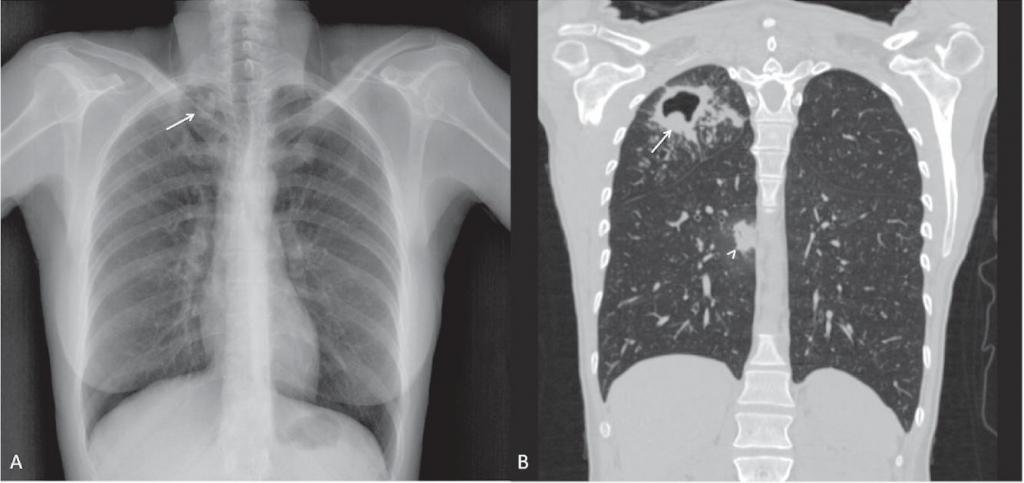

На рентгенограмме обнаруживается при туберкулезе:

- Диссеминированном. Множество мелких, хорошо очерченных, или более крупных пятен, есть каверны.

- Очаговом. Уплотнение находится не ниже 2 ребра, вокруг могут быть фиброзные тяжи, усилен легочный рисунок.

- Инфильтративном. Уплотнения правильной округлой формы на рентгеновском снимке в верхней легочной доле.

Инфильтративная форма

Это наиболее распространенная форма туберкулеза, которая встречается более чем в 60 % случаев. Она характеризуется распространенным некрозом (гибелью) ткани легкого. В зависимости от того, что показывает флюорография легких, выделяют несколько подтипов инфильтративного туберкулеза:

- круглый инфильтрат — затемнение овальной или округлой формы в верхних отделах легких, чаще всего под ключицей;

- облаковидный инфильтрат — тень однородной структуры с неровными границами;

- краевой инфильтрат — тень имеет форму треугольника, вершина которого направлена к корню легкого;

- дольковый инфильтрат — представляет собой группу слившихся очагов различной плотности;

- лобит — тень больших размеров, охватывающая целую долю легкого, имеет неоднородную структуру.

На рентгене кавернозный тип туберкулеза выглядит следующим образом:

- белая округлая тень (затемнение), в центре которой определяется черная легочная ткань (просветление);

- четкие контуры тени;

- возможно наличие так называемой дорожки к корню легкого.

Наиболее частая локализация каверн — верхние отделы легких, под ключицей.